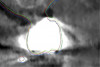

Fig 12. Thin (1 mm) panoramic reconstruction of a patient presenting with multiple prostheses of metal density. The results of the registration between the CBCT and the stone model will be evaluated in the area of the maxillary right first molar.

Figure 12

Fig 13. Thin (0.2 mm) slice at the level of the maxillary right first molar shown in Fig 12 with the STL file of the surface model registered. In this case no scanning appliance was used. Note the blooming effect produced by the artifacts at the level of the first molar.

Figure 13

Fig 14. Close-up view at the level of the maxillary right first molar shown in Fig 12 with the outlines of the registered STL stone models to the CBCT anatomy, using various methods. Green outline: automatic registration plus manual fine-tuning, no scanning appliance. Red outline: landmark registration using a scanning appliance that was CBCT scanned; in this case the STL file of the model teeth was first produced by DICOM to STL conversion, and the registration to the CBCT anatomy followed. Blue outline: landmark registration using a scanning appliance that was CBCT scanned; in this case the registration was accomplished based on the voxels of the glass beads of the scanning appliance, and then the STL file of the stone model was produced. Differences of up to 1 mm can be noted among the three methods.

Figure 14

Fig 15. Differences in the registration outcome of the stone model among the three different methods described in Fig 14 were calculated with a metrology software. The mean absolute difference was 0.618 mm, but the signed differences ranged from -2.1 mm to 5.6 mm.

Figure 15